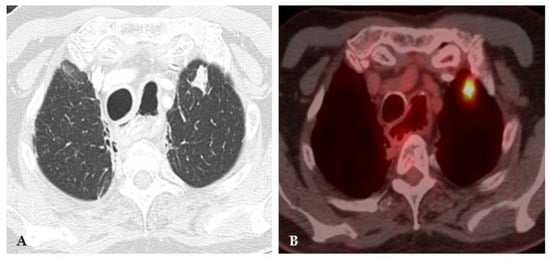

2.1. Lung Nodule or Mass

| Lung Nodule or Mass | Non-Resolving Pneumonia | Chronic Cavitating Disease | Disseminated Infection | Bronchiectasis & Asthma | |||||

| Adenopathy | Coccidioidomycosis Histoplasmosis | Consolidation + large nodules/masses | Blastomycosis Cryptococcosis Paracoccidioidomycosis | Grape-skin cavities + Lymphadenopathy | Coccidioidomycosis | Miliary ARDS Extrathoracic | ++ Histoplasmosis Coccidioidomycosis | High-attenuation mucus plugging Finger in glove | ABPA |

| Lung Mass | Cryptococcosis Blastomycosis | Adenopathy | Coccidioidomycosis Histoplasmosis | Calcified nodes | Histoplasmosis | ||||

| Flip-flop node SUVmax > lung mass | Granulomatous Infection | ||||||||